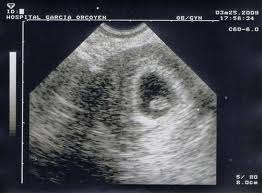

¿Porqué mi embrión, aunque tenía latido, era más pequeño de lo normal y acabó en aborto?

Buenas tardes, he tenido dos abortos uno bioquimico en abril y otro a las 8 semanas en julio. El segundo embarazo mi embrion con 7 semanas media unicamente 3 mm aunque tenia latido, era más pequeño. Me decía que habría ovulado más tarde pero el caso es que no, solo mantuve esa relacion y es imposible que me quedara otro dia. Me he realizado los analisis de abortos de repeticion, todo esta bien excepto la proteina S al 65 %, cuando el limite lo ponen del 70% al 140%, y el anticoagulante lupico con positivo debil. La hematologa me dijo que esa no sería la causa. El caso es que todo lo demas me ha salido bien, incluso la FSH del día 3, me ha salido 5. ¿¿¿Porque el embrion era más pequeño??. Gracias por la respuesta

En relación a la información que nos solicitas comentarte que esos valores de trombofilias parecen alterados. Quizás te recomendamos una segunda opinión. El embrión es más pequeño cuando por alguna causa no puede seguir creciendo. Ya sea que no logremos llegar a verlo como en un embarazo bioquímico o como en los casos que deja de crecer es por algo que le impide desarrollarse con normalidad.